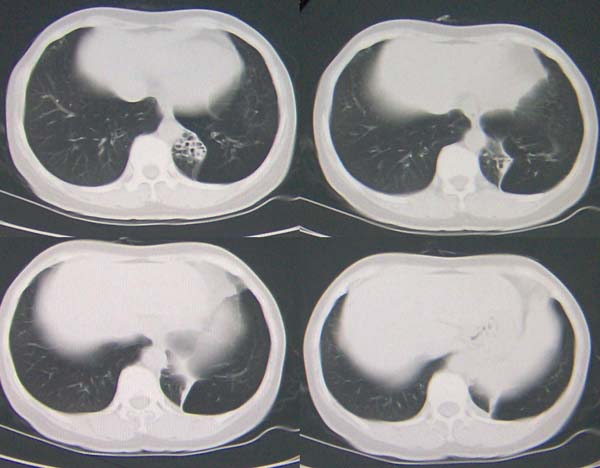

左下肺纤维条索并局部胸膜肥厚

左下肺支气管扩张;支气管炎;左下肺纤维条索并局部胸膜肥厚

左肺舌叶及右肺下叶背段斑片状低密度影,左肺下叶内基底段网格状阴影,周围肺野透亮度增高,结合临床咳嗽、发热,38度,无咯血及反复感染病史,考虑双肺炎症,左下肺发育不良。建议抗炎治疗后复查或增强与左下肺隔离症鉴别。